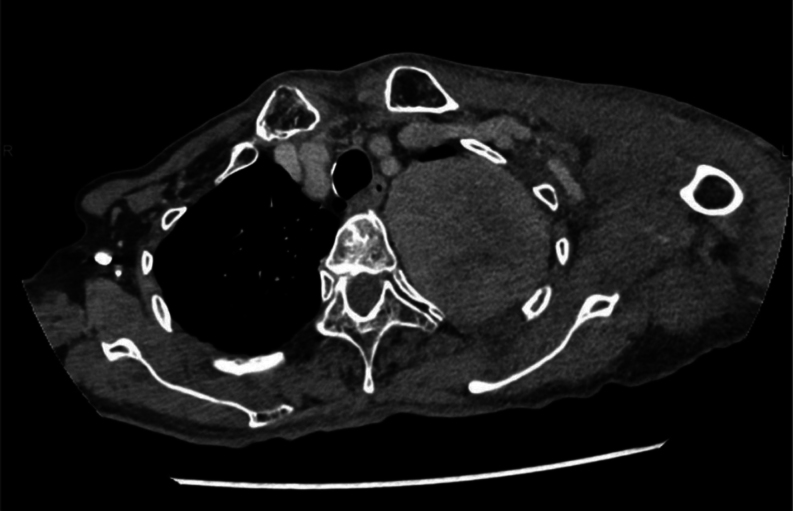

Summary: An 82-year-old woman with a 60-year history of a lung tumor presented with hypoglycemia. Non-islet cell tumor hypoglycemia (NICTH) was suspected; however, her hypoglycemia stabilized with supplemental food. She was discharged, based on her wishes, and planned to undergo surgery later. After discharge, the hypoglycemia worsened rapidly and required immediate resection. Postoperatively, the hypoglycemia resolved. Western immunoblot analysis confirmed the presence of big insulin-like growth factor 2, confirming NICTH. This patient experienced the rapid progression of symptoms after an unprecedentedly long-term asymptomatic state. Therefore, when NICTH is suspected, early intervention is recommended regardless of the presence of asymptomatic state.

Learning points: In patients with NICTH, the onset of hypoglycemia is usually within a year of tumor detection, and few reports regarding long-term asymptomatic NICTH have been documented. NICTH can cause rapidly progressive symptoms after a long-term asymptomatic state, as in this case, and an asymptomatic state does not preclude the necessity for intervention, especially when patients are at risk for malnutrition. Tumor resection is the only curative treatment for patients with NICTH, but there is no consensus regarding the timing of surgery. However, considering the possibility of rapid symptom progression, patients should be examined and treated in a timely manner.